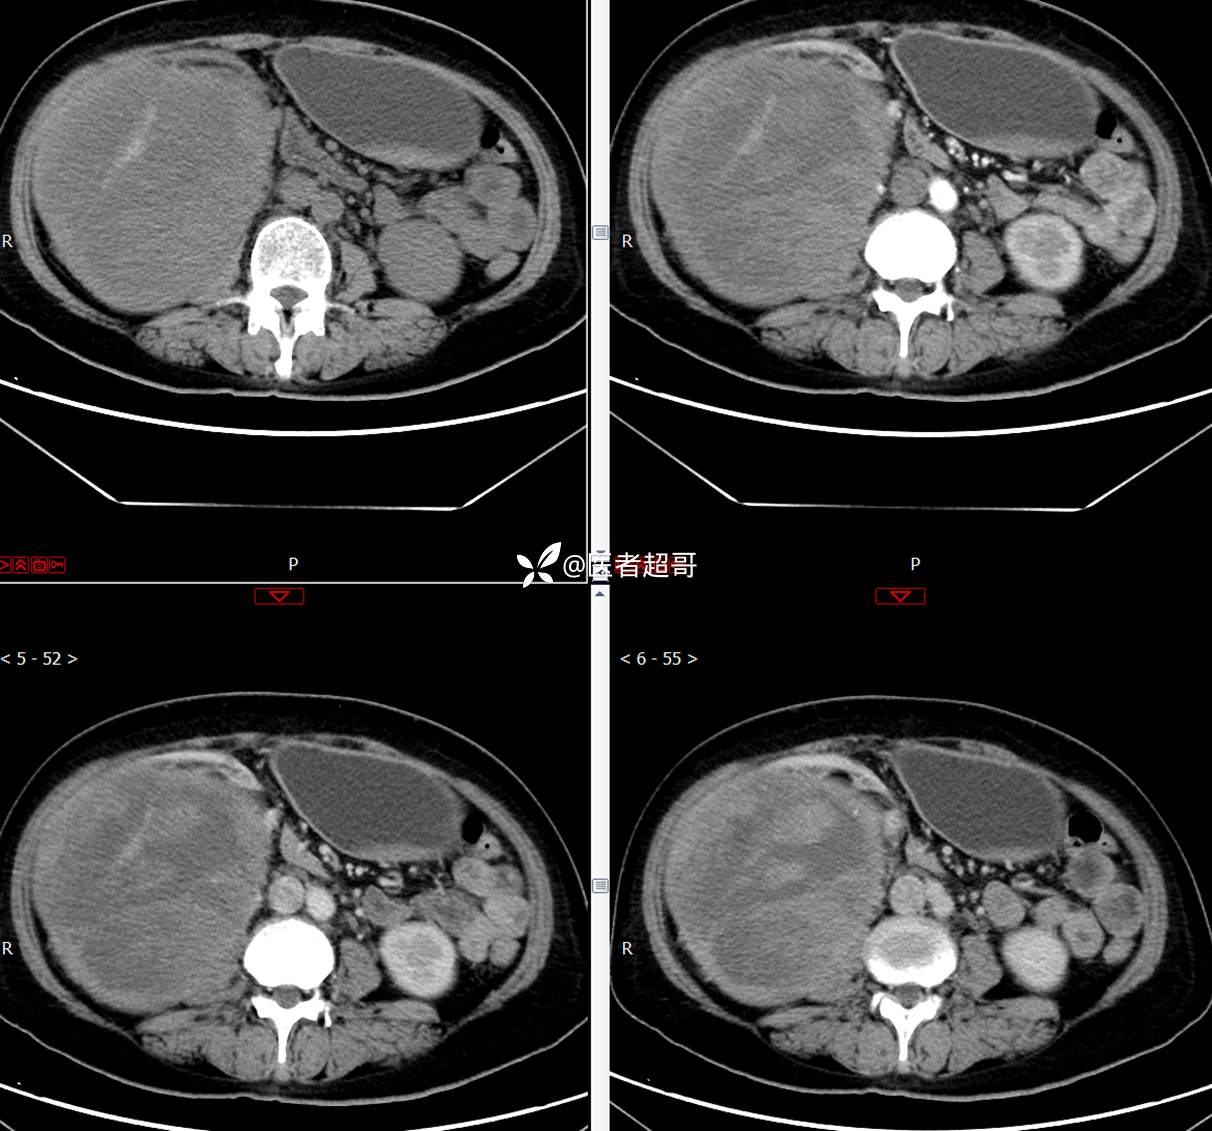

现病史:患者1周余前发现右上腹有一半球形巨大肿物,约18cm*15cm大小,既往贫血病史3年余,诉乏力,易疲劳,偶有头晕,活动后心悸,无腹痛、腹胀,无恶心、呕吐,无尿频、尿急、尿痛,无排尿困难,患者为求进一步治疗,来我院消化内科就诊,门诊行肝.胆.胰.脾.肾彩超示:右肾上部囊实性占位,范围约18.0cm×11.7cm×16.4cm,边界清,形态规则,建议进一步检查,腹膜后实性结节。我科遂以“肾肿物”收治入院,患者自发病以来,神志清、精神可,睡眠、饮食可,二便正常,体重、体力略有下降。